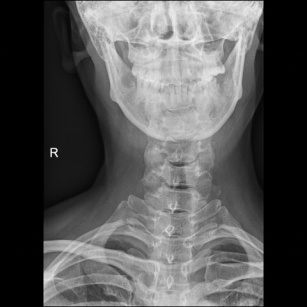

术前X片

术前CT 术前MRI